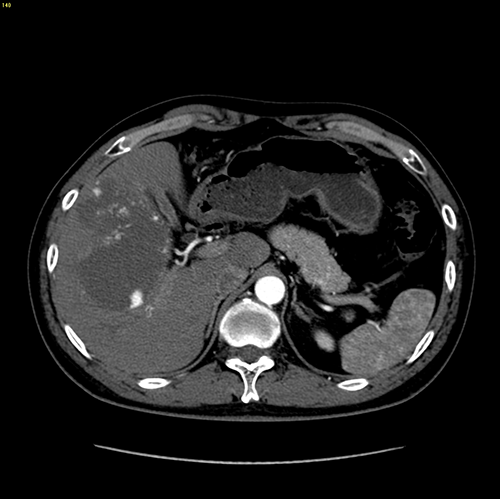

右肝巨大肝血管瘤---S56巨大肝血管瘤切除